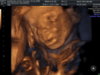

ja już po połówkowym i wszystko ok.

i nie ma wątpliwości będzie Maksiu:

IMG_20140901_1_1.jpg

u prywatnego młody ważył 358 g, a dzień później na nfz 419g